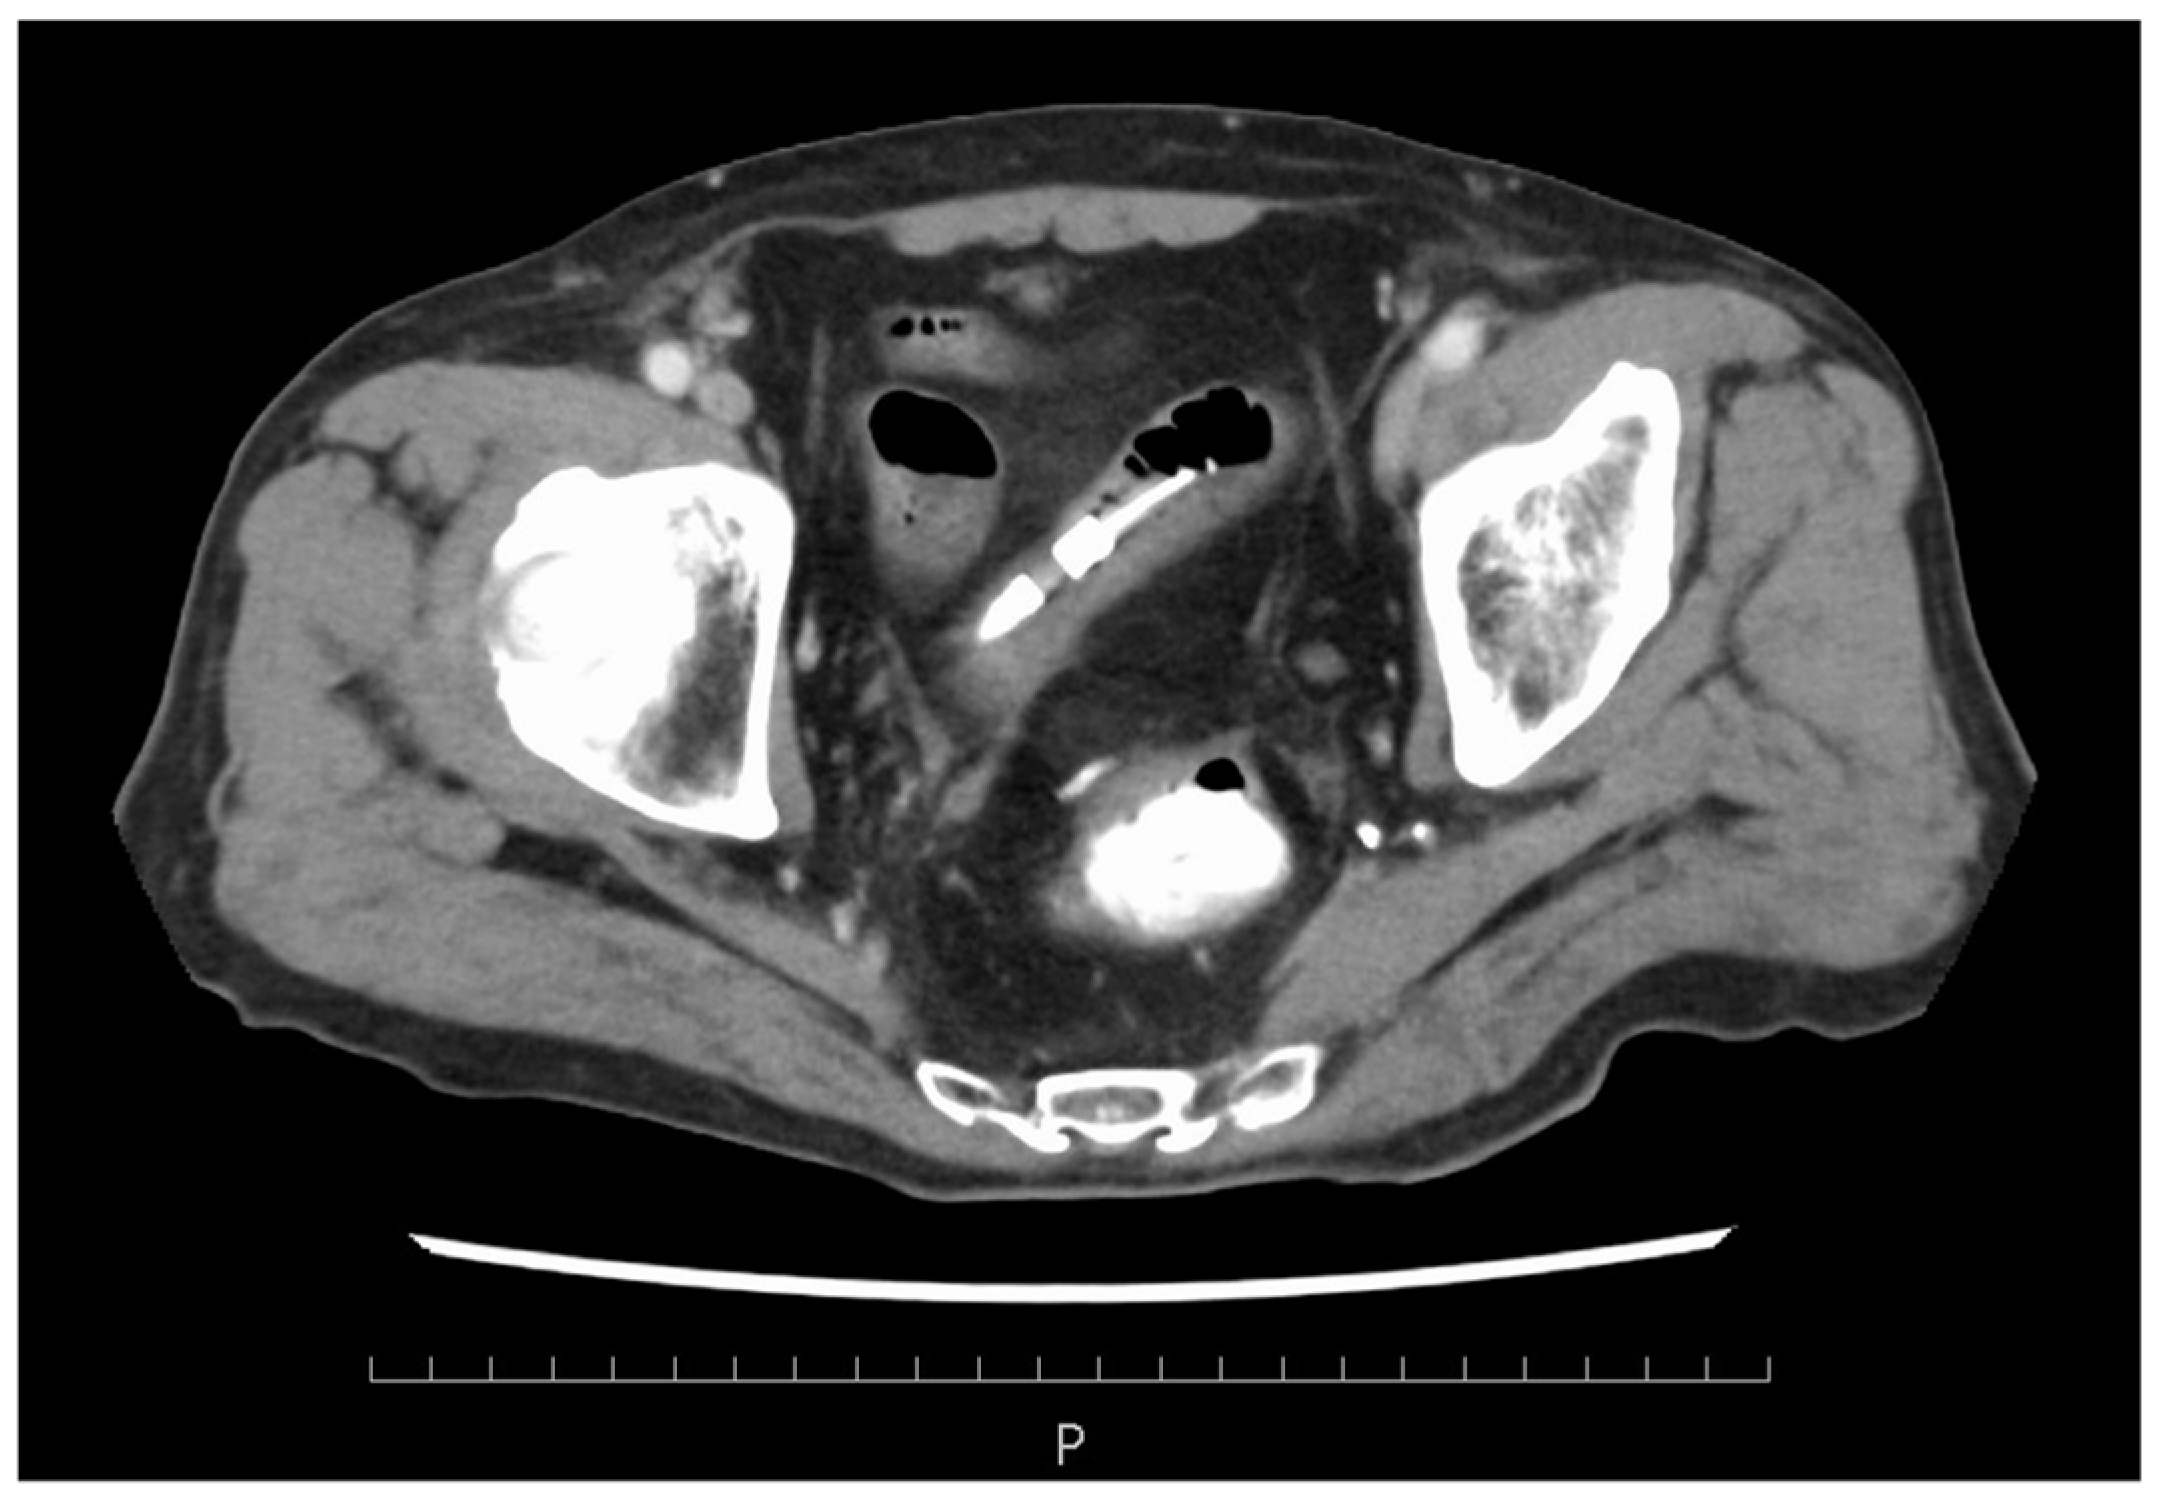

2. Case Presentation